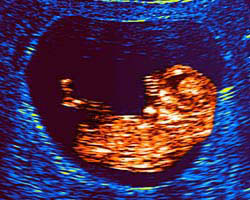

Ecografia de 9 semanas

Na 9ª semana de gravidez o embrião mede entre 13 e 17 milímetros, aproximadamente, desde o cocuruto até às nádegas.

Idade do embrião: 7 semanas.